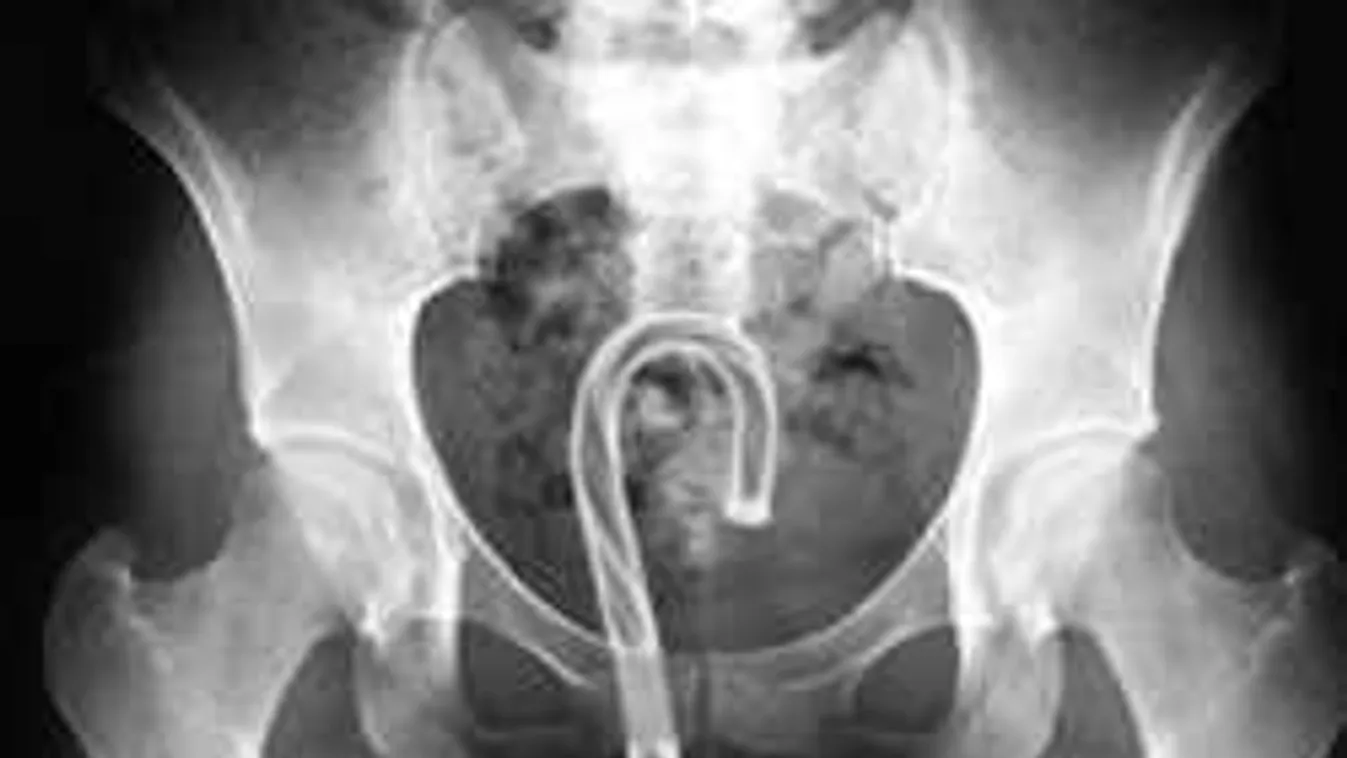

SZEX & MÁS 2019. 01. 17. Nem hiszed el, miket találnak a nők vaginájában - sokkoló röntgenfotók! Egészen elképesztő felvételeket mutatunk. Nem fogsz hinni a szemednek!

SZEX & MÁS 2019. 01. 16. Még a rendőröket is sokkolta, amit a nő vaginájában találtak A valóságban bizonyára bizarr élmény lehetett, de aki a hírt hallotta, az is teljesen megdöbbent. Sokan ugyanis el nem tudják képzelni, ilyesmi egyáltalán hogyan férhet be oda?